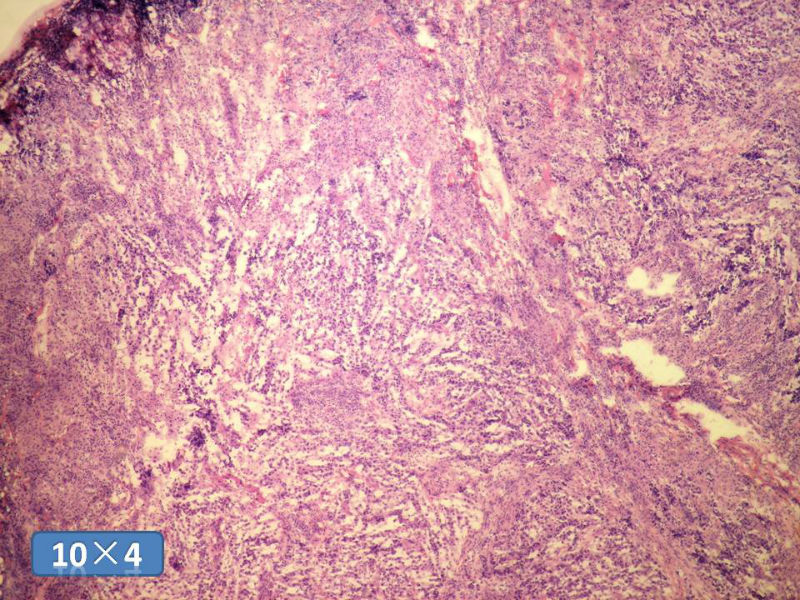

女性,50岁,乳腺肿物,冰冻切片(图1-25)

HE